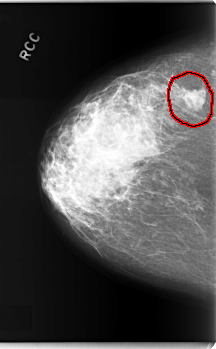

C_0208_1.RIGHT_CC

RIGHT_CC LINES 5928 PIXELS_PER_LINE 3664 BITS_PER_PIXEL 12 RESOLUTION 50 OVERLAY

FILE: C_0208_1.RIGHT_CC.OVERLAY

TOTAL_ABNORMALITIES 1

ABNORMALITY 1

LESION_TYPE MASS SHAPE IRREGULAR MARGINS MICROLOBULATED

ASSESSMENT 5

SUBTLETY 5

PATHOLOGY MALIGNANT

TOTAL_OUTLINES 1

BOUNDARY